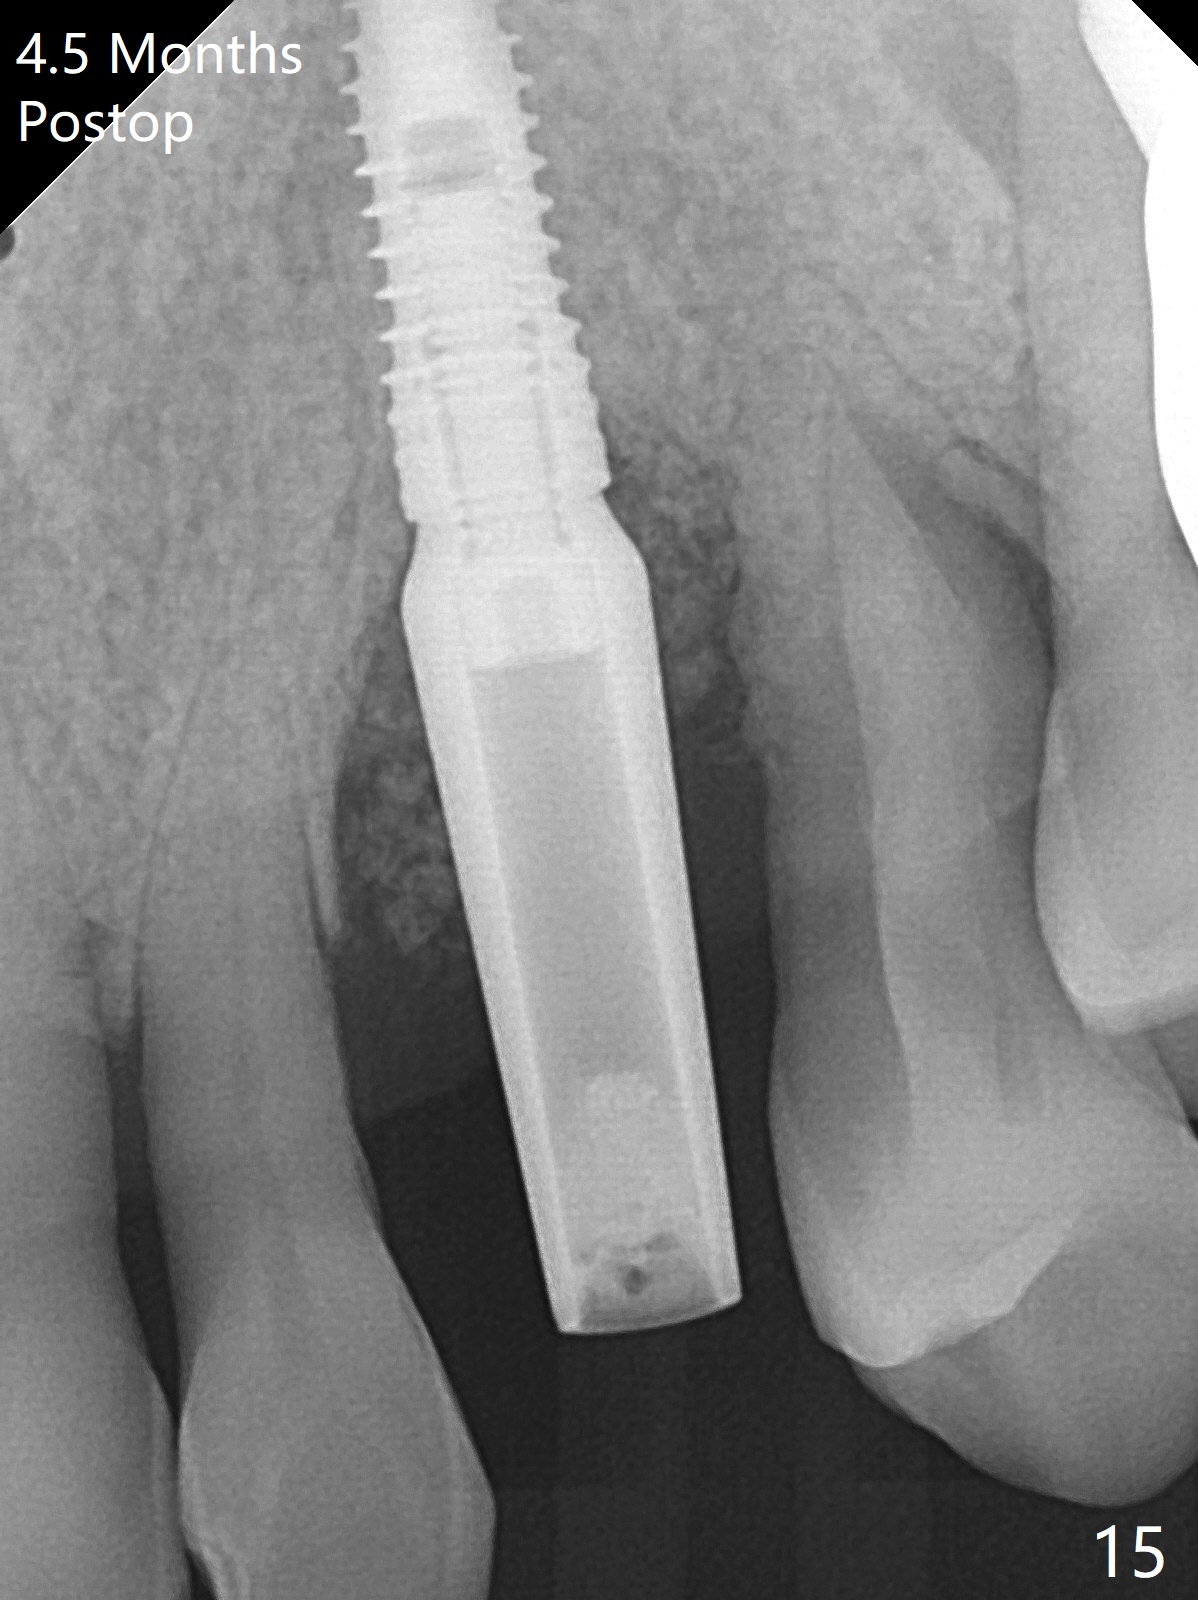

A 62-year-old man with generalized chronic periodontitis returns with chief complaint of loose tooth at #11 (Fig.1). Although a buccal fistula (Fig.1 <) is closer to #12 than to #11, percussion is more severe at #11 than 12. The buccal plate of #11 is missing, but it is possible to place a narrow immediate implant because of the wide alveolus (Fig.2). Since the gingiva is ~ 10 mm long, a mill abutment is to be used (Fig.3,5). In fact the fistula communicates with #11 extraction socket. After debridement, osteotomy is initiated (Fig.4) for a 3.8x10 mm implant ~ 35 Ncm, followed by seating a 4.5x2 mm mill abutment (Fig.5). Abundant sticky bone is placed in the remaining socket (for buccal plate reconstruction) and against the root surface of the neighboring teeth (Fig. 6 * (#10,12)). Finally 2 pieces of PRF membranes are utilized to facilitate repair of the buccal soft tissue defect (Fig.7 *). The root prominence of the canine seems to be maintained by the bone graft (Fig.8 C). Acrylic dressing holding the PRF membranes in place remains in situ with the healthy gingiva buccal (Fig.9) and palatal (Fig.10) 11 days postop. Note the acrylic locking into the undercuts of the neighboring teeth (*). 经过一段摸索发现离心每分钟1500转5分钟后,抽取上清液,接着再离心10分钟剩余上清液就形成血小板块,压制后便是血小板膜,后者似乎有助于软组织愈合,而上清液用来制备骨块,帮助硬组织生长。利用这个原则讨论以下病例治疗。The gingival margin gains ~ 5 mm 6 weeks postop when the acrylic dressing is removed (Fig.11,12 (<: previous one), as compared to Fig.7,8). 治疗结束时尖牙牙龈缘高于第一双尖牙(图七,八),六个星期后,尖牙牙龈缘却低于双尖牙(图十一,十二(箭头:原始牙龈缘))。术后2.5,4.5月基台周围牙龈似乎能与钛合金附着,防止细菌进入深部植体(图十三,十四)。临时牙冠脱落多次,可能与mill abutment太光滑有关,所以颊侧,舌侧磨成平面(图十四)。取模时好像不必取出基台清洗(仿佛没有炎症),原位用树脂延长基台。术后5个月CT显示颊侧骨板再生(图十六-十八)。取模时并没有用树脂加长基台;粘固时,牙冠颜色理想,但是照片中并不是如此(图十九,二十),颊侧骨板没有塌陷。术后11个月基台颊侧骨板没有萎缩(图二十一:B);3d图像:骨壁完全形成(图十六对比:部分形成)。密度也增高(图二十二:B),与术后五个月比较(图十七)。术后十一个月,粘固后五个月角化龈存在(图二十三),牙冠颈部有金属颜色透出,是因为二段式基台太粗了(最细4.5毫米),可以请实验室在牙冠内部涂opaque material而减轻。